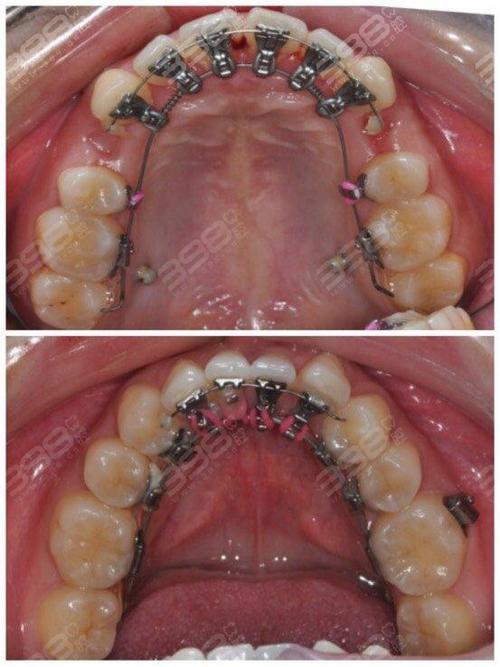

- 金属托槽矫治器: 最传统,性价比高,力量大,适用范围广,有普通金属和自锁金属(复诊间隔长,舒适度稍好)。